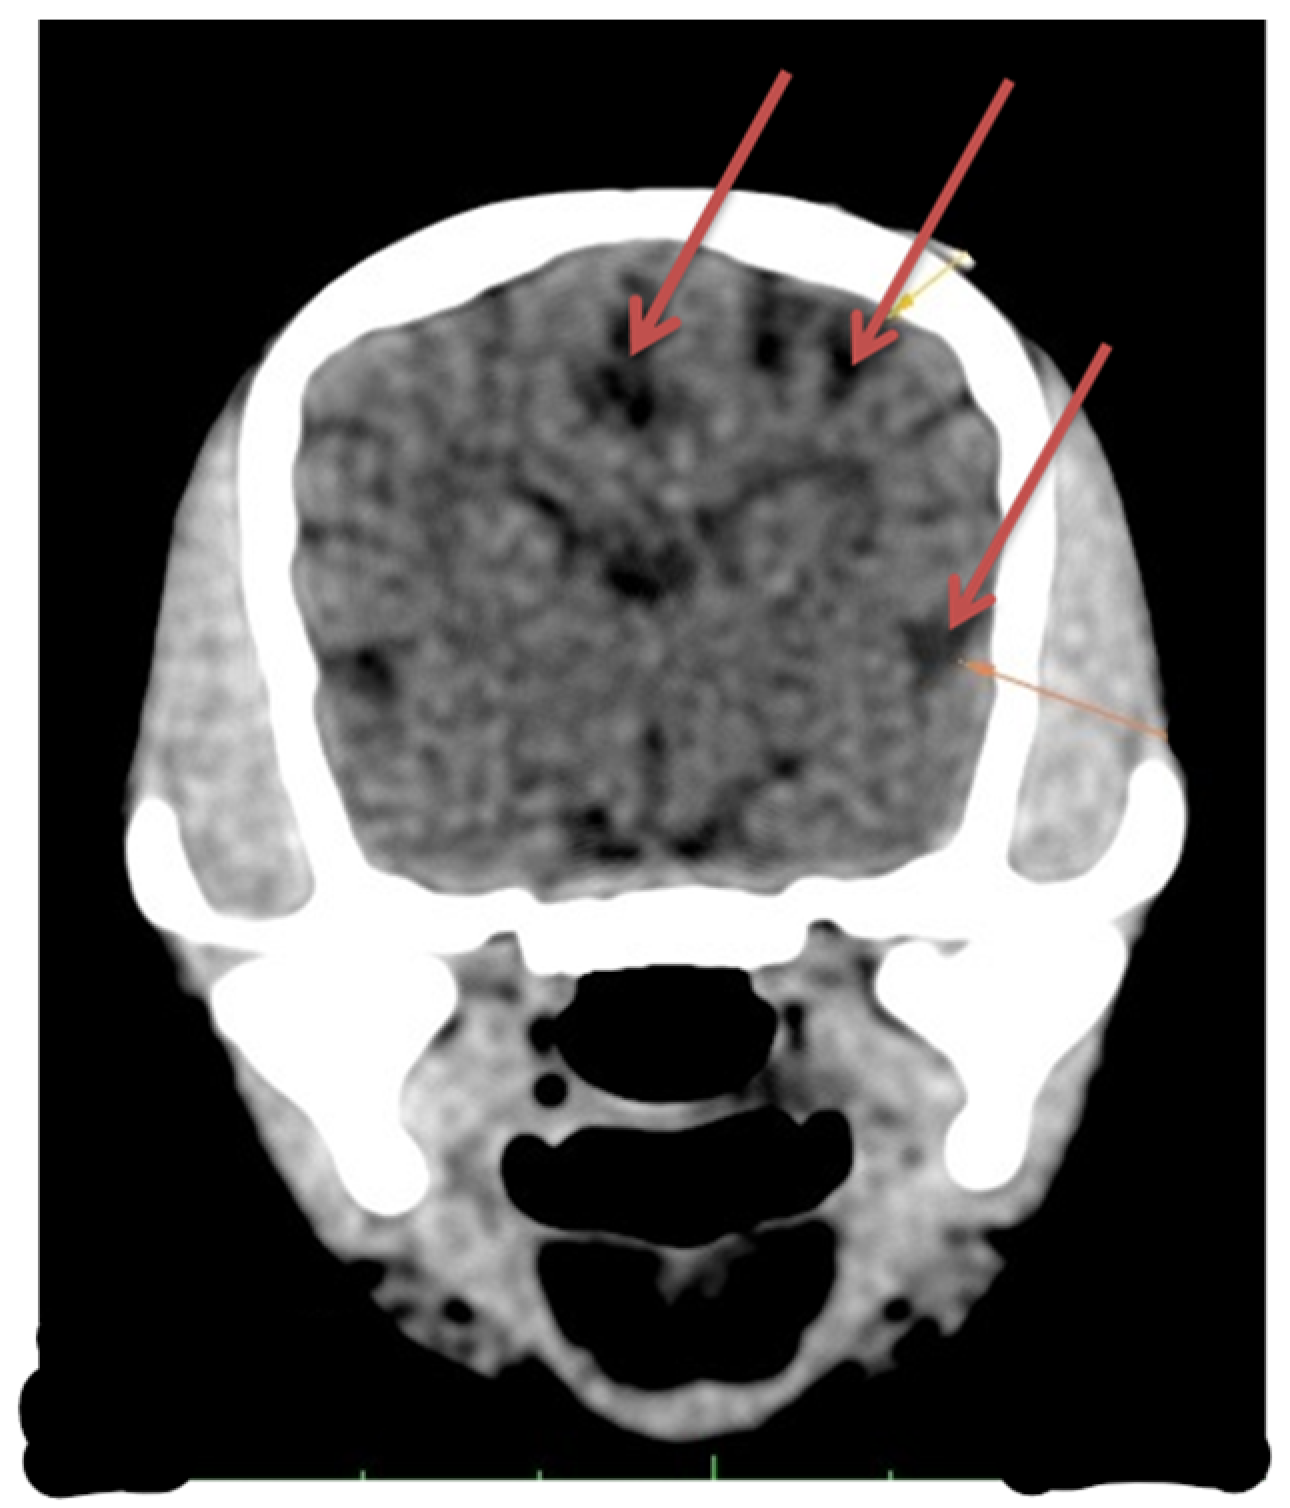

Laboratory tests showed a hemogram with neutrophilic leukocytosis, and serum biochemistry revealed abnormalities in routine hepatic markers, including AST 130 U/L (normal range of 14–45 U/L), ALP 207 (normal range of 20–150 U/L), and GGT 9 (normal range of 0–7 U/L). An abdominal ultrasound examination (My Lab 40 ultrasound machine, Esaote Pie Medical, Maastricht, The Netherlands) revealed a congenital portosystemic shunt (Figure 1) (in comparison to a physiological aspect, Figure S1), for which the patient was recommended to undergo bile acid testing and advanced imaging (abdominal CT). For a rapid diagnosis and due to financial reasons, the owner agreed to advanced imaging, and temporarily declined the bile acid testing. CT examination under chemical restraint (Ketamine, Kepro, Deventer, The Netherlands, at 0.1 mg/kg IV and medetomidine, Domitor, Orion Pharma, at 0.05 mg/kg IV) revealed a large extrahepatic porto-caval shunt (Figure 2) associated with multiple conical cortical brain lesions that were hypodense, with reduced or absent contrast uptake, along with more extensive biconvex lesions, including along the cerebral sulci (Figure 3). A final diagnosis of portosystemic shunt and presumed hepatic encephalopathy was established.

Figure 3. Cerebral CT exam in a Bichon dog, 3 months old, with portocaval shunt. Multiple hypoattenuated lesions with little to no contrast enhancement, some located in the cortex with a conical shape, others more extensive and biconvex, as well as along the cerebral sulci.